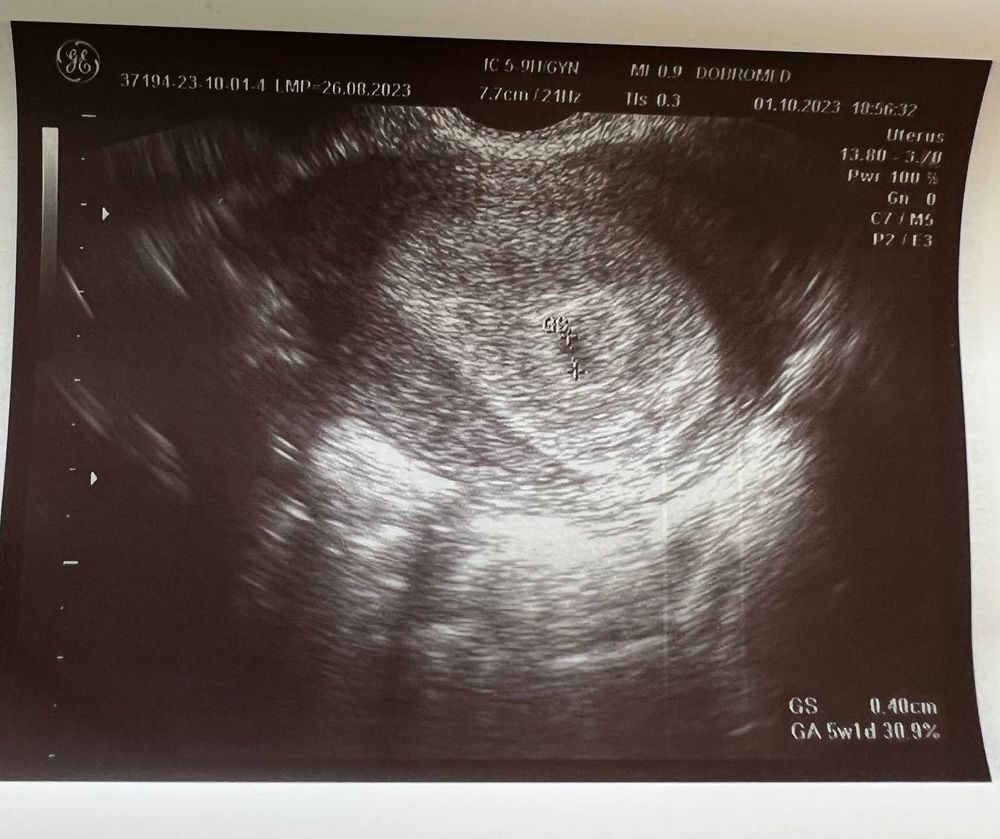

Вчера (1 октября) сходила на УЗИ, беременность подтвердили, маточная.

Размер плодного яйца 4 мм.

Но не видно желтое тело, и мутное содержимое плодного яйца (как она сказала). Меня напугала очень узистка... мол, может быть замершая беременность.

Если есть специалисты тут - пожалуйста, посмотрите снимок

Ниже фото заключения и УЗИ: